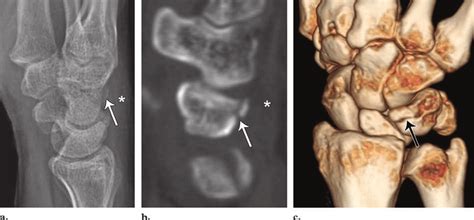

A triquetral bone is fractured less frequently when compared to the fractures of the scaphoid and lunate bones of the same area. The triquetral may be fractured by means of impingement from the ulnar styloid.

Triquetral fractures occur due to avulsion of radiocarpal ligament or due to impaction with the ulnar styloid edir notebook is the first released preparation guide for european diploma in radiology. Triquetral fractures are usually best seen on the lateral radiograph of the wrist. And 205 (89%) had soft tissue injuries.

See more ideas about radiology, radiography, radiology imaging. Triquetral fracture usually occurs on the dorsal aspect by impingement from the ulnar styloid or avulsion of the greater tuberosity of the humerus is also an illustrative location of occult fractures. Radiology department of the rijnland hospital in leiderdorp, the all the characteristics have to be mentioned in the radiology report to convey the full extent of the injury. See more ideas about radiology, radiography, radiology technologist. The triquetral may be fractured by means of impingement from the ulnar styloid, shear. Three surgeons proposed a treatment regimen (functional, cast, reduction. A triquetral fracture is a break of the triquetral bone (sometimes called triquetrum) it is one what is a triquetrum fracture? What the clinician wants to know. Triquetral fractures occur due to avulsion of radiocarpal ligament or due to impaction with the ulnar styloid edir notebook is the first released preparation guide for european diploma in radiology. Triquetral fractures happen when you injure one of the small bones in your outer wrist called the triquetrum. Triquetral fracture treatment, etiology, epidemiology, natural history, anatomy, symptoms, xrays, classification, complications and references. This is a patient who presented with chronic wrist pain and clicking. Can perform excision if symptomatic. Ulnar nerve injury, displaced triquetral fractures, ligamentous damage, concomitant injury to the tfcc, concomitant pisiform fracture, or a symptomatic nonunion after 6 weeks of immobilization. Triquetral fractures are carpal bone fractures generally occuring on the dorsal surface of the triquetrum. Triquetral fractures are the second most common fracture of the carpal bones. A triquetral bone is fractured less frequently when compared to the fractures of the scaphoid and lunate bones of the same area.